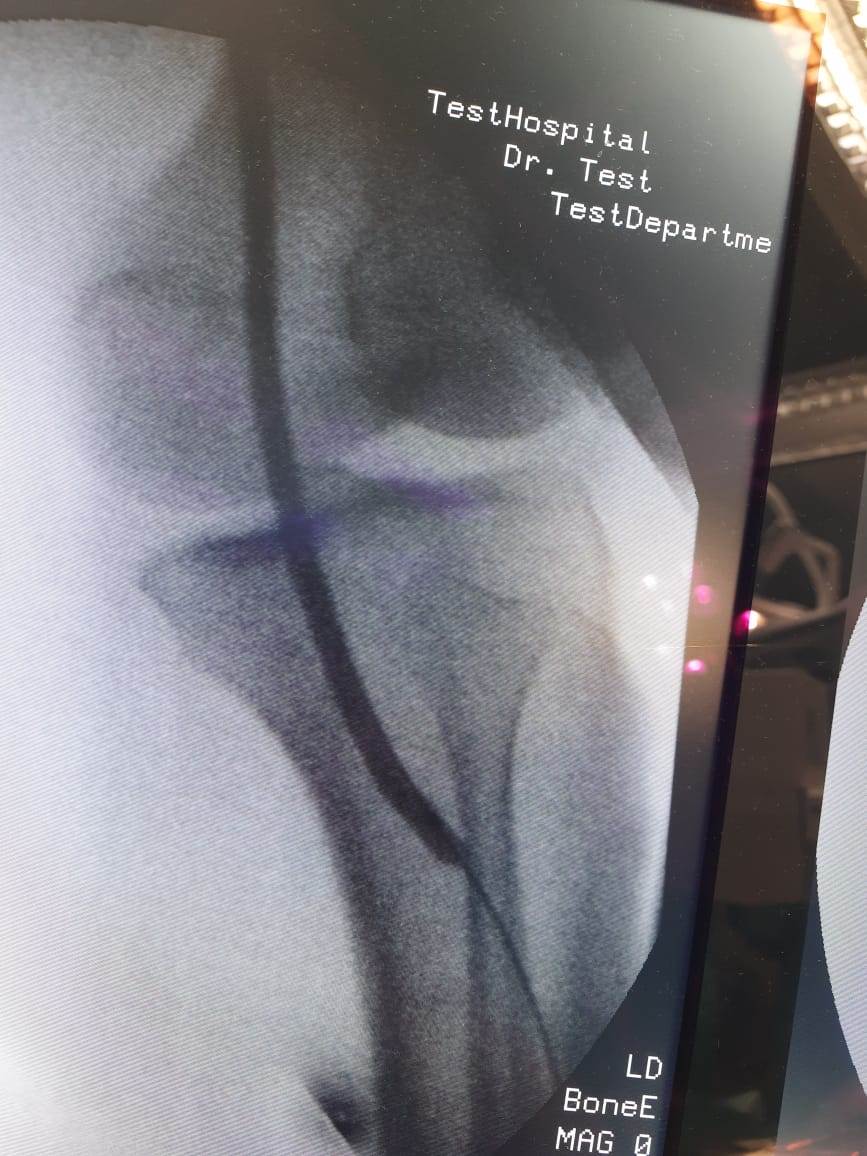

وأوضحت الهيئة برئاسة الدكتور أحمد السبكى رئيس مجلس الإدارة، أنه فور حضور المريضة محولة من وحدة صحة القرايا إلى مستشفى حورس التخصصي، بنظام الإحالة الطبية المعمول به في نظام التأمين الصحي الشامل الجديد، تم إجراء الفحوصات الطبية اللازمة لها، وتبين أنها تعاني من قصور حرج بالدورة الدموية بالطرف السفلي الأيسر وغرغرينا بالقدم نتيجة انسداد الشريان الفخذي والمأبضي الأيسر؛ وعليه تم عمل توسيع للشرايين باستخدام البالونات الموسعة واستعادة الدورة الدموية حتى القدم وإنقاذ ساق المريضة من البتر، وهي الآن بحالة صحية جيدة وحالتها مستقرة.

وأضافت أن من قام بإجراء العملية بنجاح للمريضة فريق من أمهر أطباء الأوعية الدموية بالمستشفى.